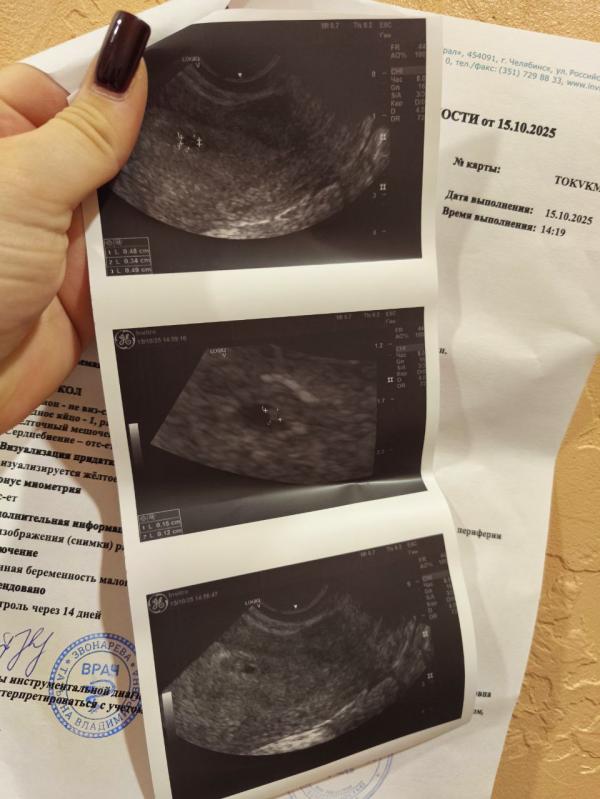

Нашли плодное яйцо на УЗИ: радостная новость о беременности

Нашли сегодня плодное яйцо, все в порядке, мы счастливы 🥰